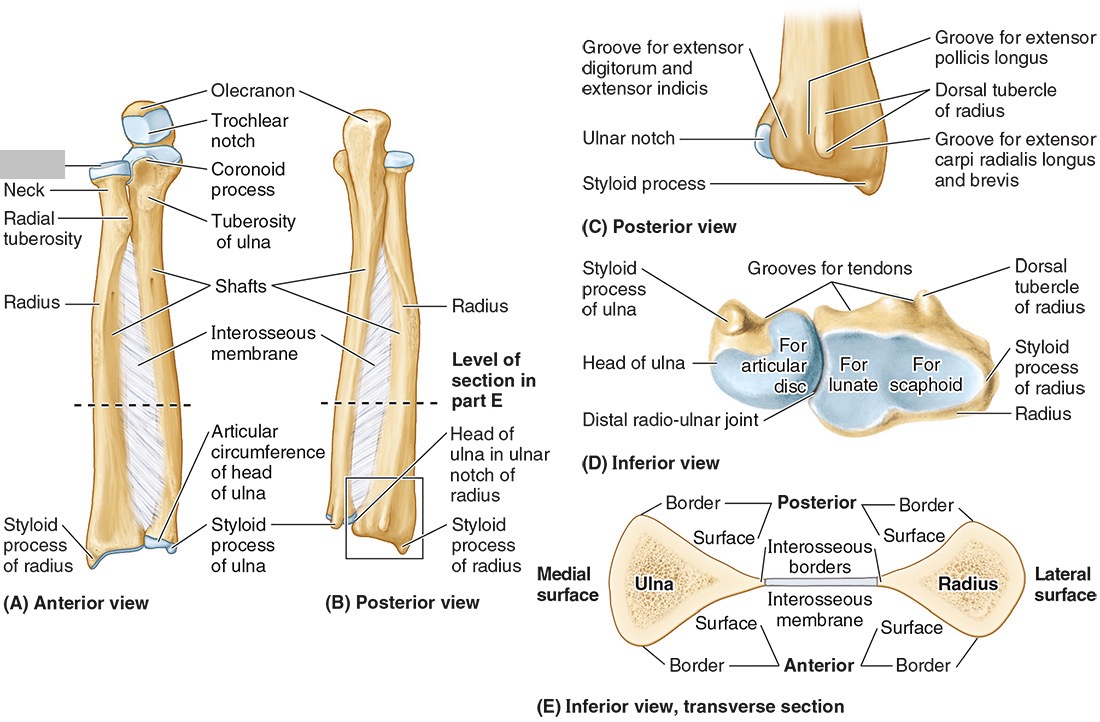

What bones connect to the humerus at the elbow?

The radius and ulna

The ______ connects to the carpal bones of the hand at the wrist joint. The _____ widens distally to provide the proximal articular surface of the wrist (remember, the _____ is on thumb side of the wrist!)

(all the blanks are the same word)

Radius

The head of the radius

The neck of the radius

The radial tuberosity

The ulnar notch

The styloid process

The ____ is the medial forearm bone

Ulna

the olecranon (superior)

The coronoid processes (inferior)

The trochlear notch

The tuberosity of the ulna

The radial notch

The head of the ulna

Distal radio-ulnar joint